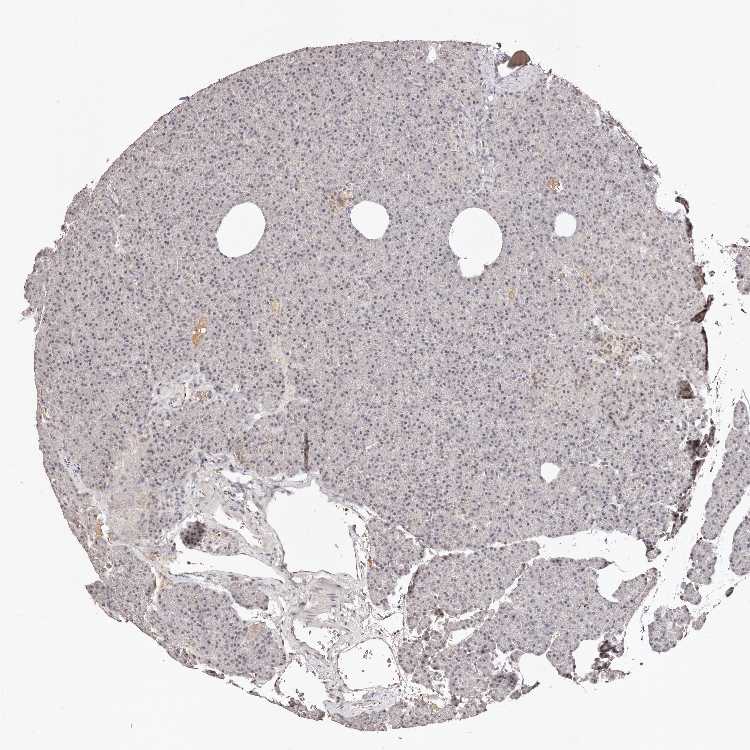

PANCREAS - Antibody stainingi

Antibody staining in the annotated cell types in the current human tissue is reported as not detected, low, medium, or high, based on conventional immunohistochemistry profiling in selected tissues. This score is based on the combination of the staining intensity and fraction of stained cells.

Each image is clickable and will lead to virtual microscopy that enables deeper exploration of all samples and also displays staining intensity scores, fraction scores and subcellular localization as well as patient and tissue information for each sample.

Antibody HPA029390Antibody HPA029391

Exocrine glandular cells MediumNot detected

Pancreatic endocrine cells LowMedium